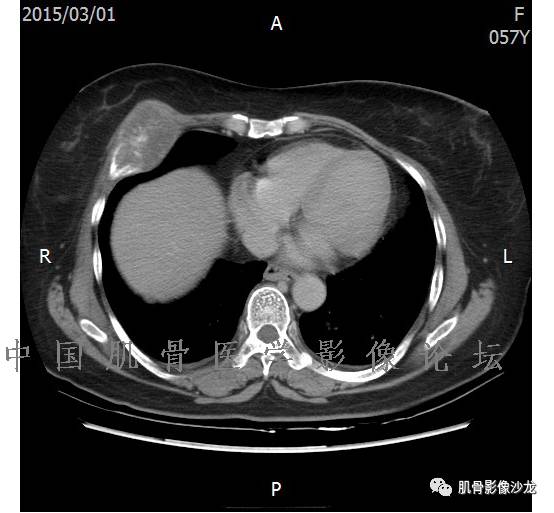

雪舞 :第二例,位于骶骨,有骨质破坏并有软组织肿块,软组织肿块边界清

雪舞: 第二例我们能够看到破坏与软组织肿块不成比例,软组织肿块大,破坏小

雪舞 :第二例挺难的,骨质破坏是溶骨性的,局部皮质中断,软组织肿块外缘光滑

雪舞 : 软骨肉瘤的发病率居原发性恶性骨肿瘤的第三位,其特点是肿瘤内具有软骨基质

雪舞:弓形钙化,钙化比例少于面积的1/3,钙化边缘模糊

雪舞 : 都是软骨肉瘤鉴别于内生软骨瘤有意义的区别点